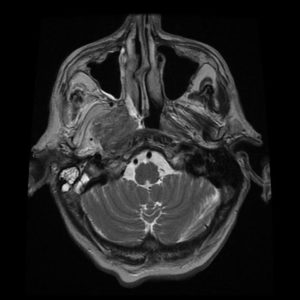

U dây VIII

Lượt xem: 162» 02-03-2019 -

U dây VIII

Lượt xem: 132» 24-11-2018 -

U dây VIII

Lượt xem: 130» 24-11-2018 -

U dây VIII

Lượt xem: 153» 24-11-2018 -

U dây VIII

Lượt xem: 147» 24-11-2018 -

U dây VIII

Lượt xem: 117» 24-11-2018 -

U dây VIII

Lượt xem: 149» 24-11-2018 -

U dây VIII

Lượt xem: 143» 24-11-2018 -

U dây VIII

Lượt xem: 158» 24-11-2018